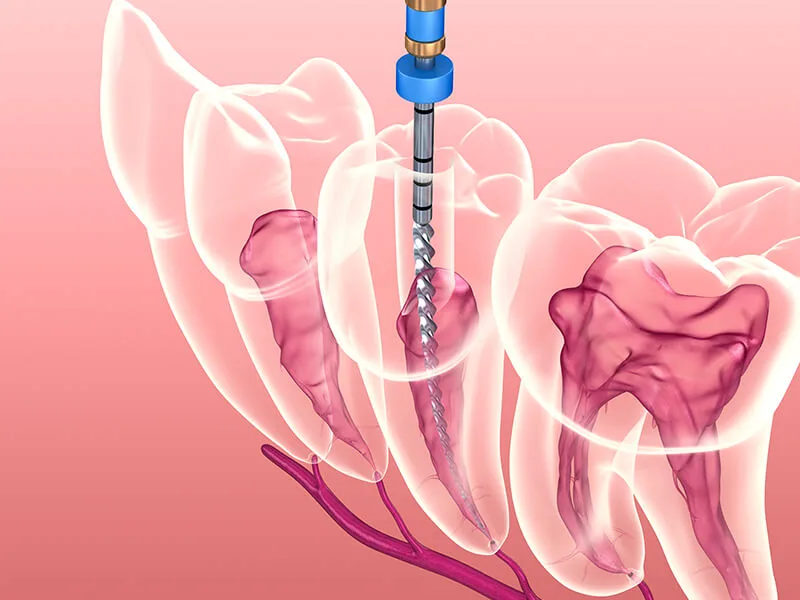

Etapas do Procedimento

Após o diagnóstico, o procedimento é realizado em etapas.

Primeiramente, o dentista anestesia a área afetada.

Em seguida, ele remove a polpa danificada, limpa e desinfeta o canal radicular.

Por fim, o canal é preenchido com materiais biocompatíveis.